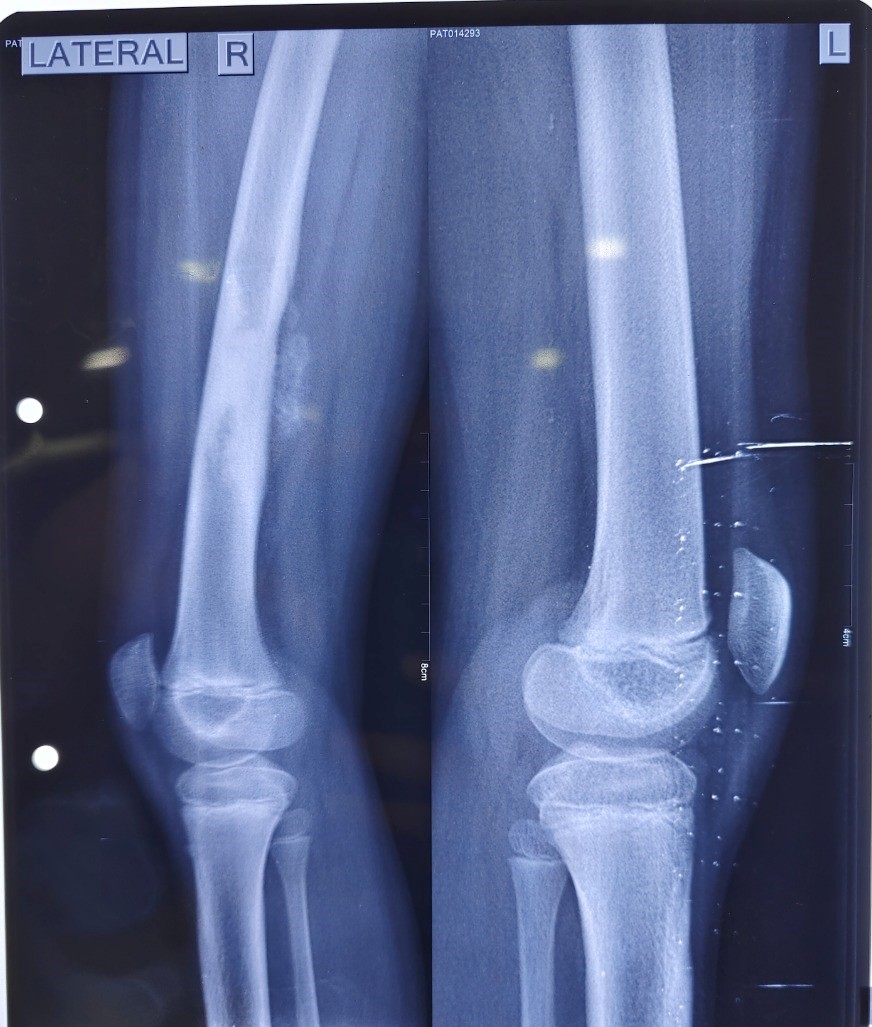

रायपुर, 26 नवंबर। बालको मेडिकल सेंटर के कैंसर विशेषज्ञों ने हाल ही में एक 10 वर्षीय लडक़ी का दाएं जाँघ की हड्डी (फीमर) के ओस्टियोसारकोमा (हड्डी के घातक ट्यूमर) का सफल इलाज किया। सर्जन्स की टीम ने कैपन्ना तकनीक नामक एक दुर्लभ प्रक्रिया को संशोधित करके इस बच्ची काइलाज किया। इस बच्ची को पहले बोन कैंसर के लिए कीमोथेरेपी दी गई थी, जिससे उससे लाभ नहीं हुआ, इसलिए डॉक्टरों की टीम ने जाँघ की हड्डी को हटाने एवं पुन:निर्माण की योजना बनाई।

जाँघ की हड्डी का पुन:र्निर्माण एक बहुत ही जटिल प्रक्रिया है और इसके लिए बहुत अधिक विशेषज्ञता और विशेष उपकरण की आवश्यकता होती है। डॉक्टरों ने एक संशोधित कैपन्ना तकनीक करने का फैसला किया, जिसमें दोषपूर्ण जाँघ की हड्डी को फीमर बोन एलोग्राफ्ट के साथ संवहनी फीबुला हड्डी के संयोजन से फिर से बनाया जाता है, जो बोनग्राफ्ट किसी अन्य व्यक्ति से उपलब्ध कराया जाता है। संवहनी फीबुला हड्डी पुन:र्निर्माण के लिए जैविकी प्रदान करती है जबकि फीमर बोनग्राफ्ट पुनर्निर्माण के लिए संरचनात्मक सहायता प्रदान करता है। केवल फीबुला हड्डी के साथ पुनर्निर्माण की सलाह नहीं दी जाती है क्योंकि यह फीमर की तुलना में बहुत पतली और कमजोर होती है। जबकि, केवल फीमरग्राफ्ट के साथ पुन:र्निर्माण के परिणाम स्वरूप ग्राफ्ट का अतिक्षय, हड्डी का न जुडऩा और घाव का संक्रमण हो सकता है, विशेष रूप से कैंसर में जहां रोगी को विकिरण दिया जायेगा।

हालांकि, इस लडक़ी के मामले में, बालको मेडिकल सेंटर के विशेषज्ञों ने कैपन्ना तकनीक को संशोधित किया, जहां विकिरण ऑन्कोलॉजिस्ट, डॉ गौरव गुप्ता और टीम के नेतृत्व में विकिरण विभाग में काटी गई फीमर हड्डी भेजी गई जिसे उच्च मात्रा में विकिरण दिया गया ताकि कैंसर कोशिकाओं को खत्म कर दिया जाए। इस बीच, प्लास्टिक और पुन:र्निर्माण सर्जन, डॉ दीपमल्या चटर्जी के नेतृत्व में पुन:र्निर्माण टीम ने दूसरे पैर से फीबुला फ्लैप काटा और माइक्रो वैस्कुलर पुनर्निर्माण किया।

विकिरणित फीमर की हड्डी को ऑपरेशन कक्ष में लाने के बाद, डॉ अंकुर गुप्ता, हड्डी रोग सर्जन, ने फीमर बोनग्राफ्ट को दो हिस्सों में विभाजित किया और डॉ. अंकुर ने आधे हिस्से में से एक को रोगी की जांघ में रोगग्रस्त फीमर की जगह रखदिया, औरउसे एक लॉकिंग प्लेट के साथ निर्धारित कर दिया।